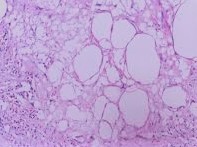

Leukemia’s and lymphomas: It is the tumor of all the haematopoitic cells of bone marrow. Leukemia’s multiply as single cell and lymphomas will in general develop as tumor mass. Tumor

Uncontrolled development of cells brings about tumors.

There are two kinds of tumors:-

Start tumor: It is typically develops of extension and remains typified in a layer of connective tissue. It isn’t dangerous and are not considered as malignant growth. For instance moles and moles.

Harmful tumor: It is portrayed by uncontrolled expansion and infinitive life expectancy of the multiplying cells. It turns out to be dynamically obtrusive. It is dangerous and allude to as evident malignant growth. For instance lung malignant growth and leukemia.